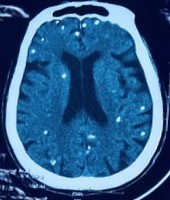

Người bệnh được chuyển lên từ tuyến trước vì rối loạn ý thức đe dọa suy hô hấp, hình ảnh cắt lớp vi tính sọ não và X-quang ngực cho thấy rất nhiều nốt cản quang trong nhu mô não và dưới da vùng ngực-bụng.

Nhiều nốt cản quang trong nhu mô não của người bệnh - Ảnh BVCC

Mặc dù xét nghiệm kháng thể IgM với sán dây lợn âm tính, các tổn thương trên X-quang gợi ý người bệnh trước đây bị nhiễm ấu trùng sán dây lợn, sau đó các nang sán trở nên vôi hóa và tồn tại lâu dài trong tổ chức. Người bệnh được điều trị theo phác đồ bệnh chính, đáp ứng và ra viện tiếp tục điều trị theo tuyến.